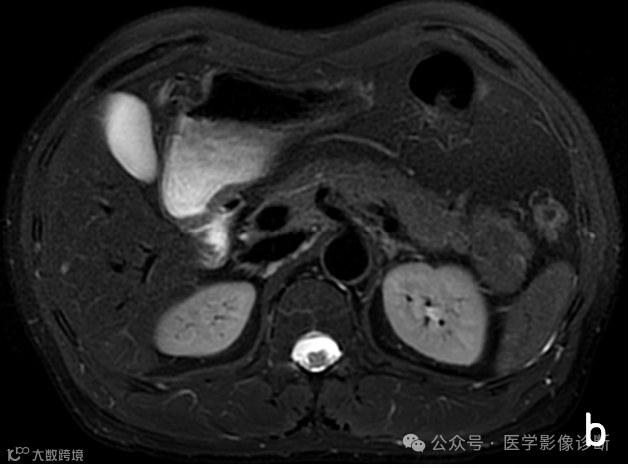

患者,男性,81岁,上腹不适半年。

胰腺尾部占位性病变,轴位MRI T1WI (a)、T2WI/FS (b)、T1WI/FS (c)、增强(d)序列均显示病变信号与脾脏相似,但是放射医生诊断为相对常见的胰腺神经内分泌肿瘤,而非罕见的异位脾脏。手术病理证实为胰腺内异位脾脏。